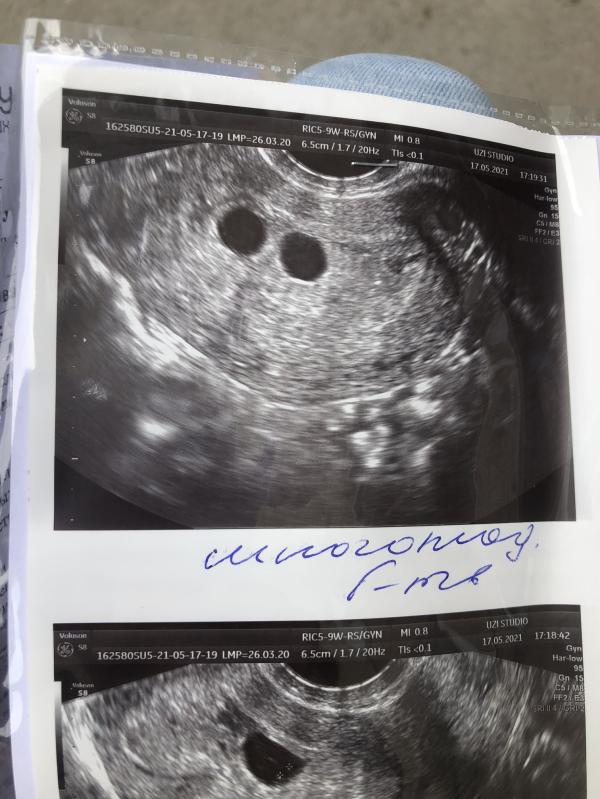

Вы только на узи сегодня узнали что беременность многоплодная? У меня нет заключения узи, но фото очень с вашим схоже😳

@lenalena92 их двое, они всегда меньше чем один. И весом будут меньше. Все будет хорошо у вас.